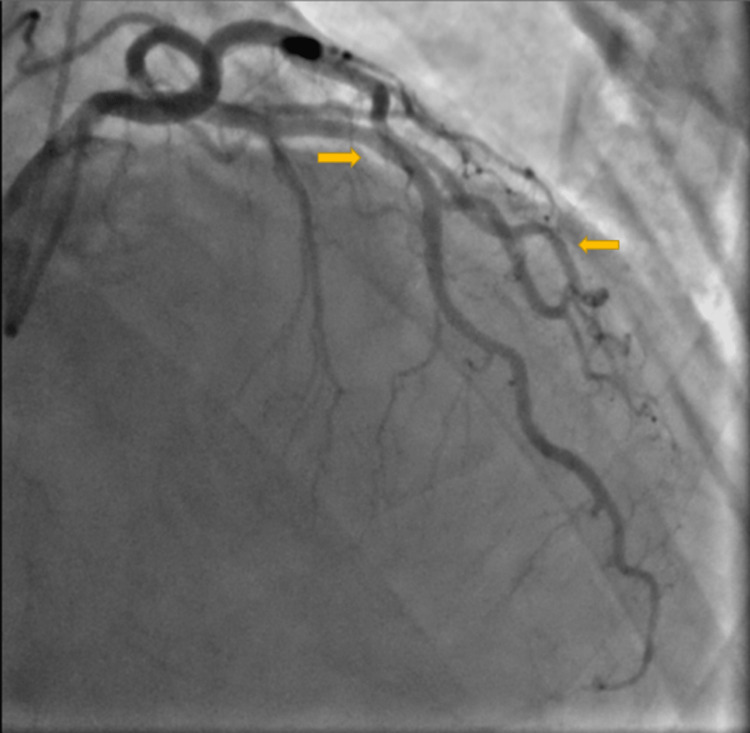

A 53-year-old male with a past medical history of hypertension, hyperlipidemia, and chronic obstructive pulmonary disease (COPD) presented with out-of-hospital cardiac arrest. The patient woke up with severe shortness of breath unresponsive to albuterol inhalers. Two hours later, the patient reported severe chest pain and was found pulseless. Emergency medical services (EMS) arrived and the patient was found to be in ventricular fibrillation. Cardiopulmonary resuscitation (CPR) was initiated, and the patient was intubated. The patient was shocked a total of five times, with four rounds of epinephrine and one round of amiodarone. Return of spontaneous circulation was achieved after 30 minutes. At the hospital, the patient’s blood pressure was 136/95 mmHg with no pressor support. Labs were significant for creatinine 1.5 mg/dl, bicarbonate 13 mmol/L, and lactic acidosis with pH 7.04. Troponins and brain natriuretic peptide(BNP) were within the normal range. EKG showed no dynamic ST segment changes on admission. UDS was positive for marijuana. The patient was urgently taken to the cath lab due to his presenting complaint of chest pain and ventricular fibrillation. Left Heart cath showed severe spasms involving all three coronary vessels responsive to intra-coronary nitroglycerin, but otherwise no significant obstructive coronary disease (Figures 1,2). He was started on a nitroglycerine drip for vasospasm.